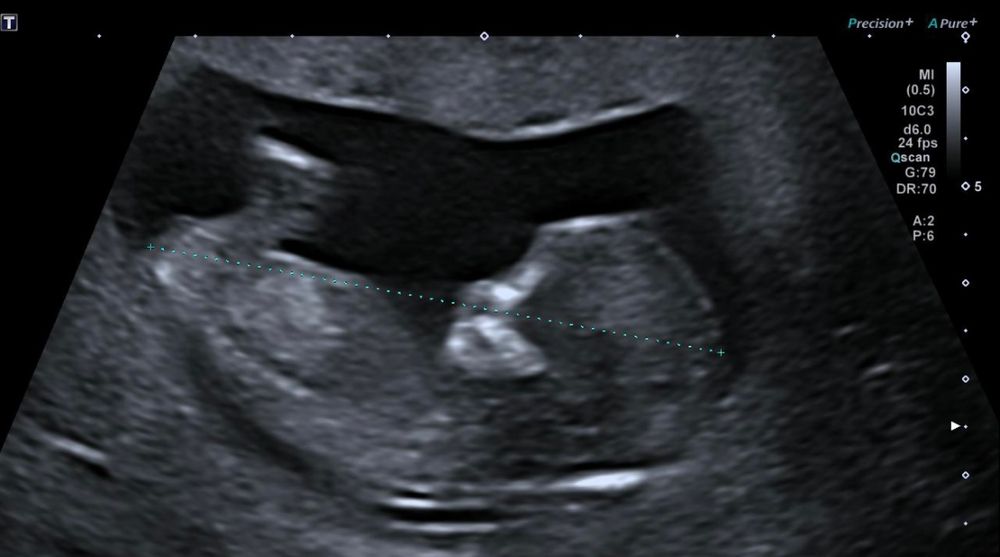

Mamepoxyi

Слишком плохо видно ,видимо не полностью его засветили )

у моей когда не полностью был тоже примерно так же )